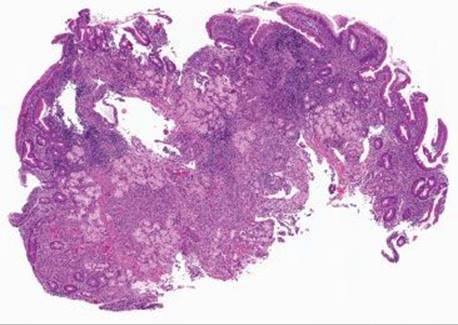

This case was received as “prominent ampulla, concerning for malignancy” (Fig. 3.313). The initial sections show duodenal mucosa with acute and chronic inflammation, gastric foveolar metaplasia, and marked reactive epithelial change (Fig. 3.313). Although these histologic features can account for a nodular clinical impression, deeper sections were pursued based on the clinical suspicion for malignancy. The first set of deeper sections were similarly concerning, but definitive malignancy was not seen. Deeper sections were repeated. And repeated. And repeated. In this case, the tissue block was exhausted and on the 38th level (!!!), clear lymphovascular invasion and infiltrating adenocarcinoma were seen (Figs. 3.314 and 3.315). When the histology does not fit the clinical scenario, consider deeper sections. When the deeper sections are not conclusive, consider repeat deeper sections or recommend rebiopsy (in this case, the patient was too unstable for a subsequent biopsy).

Figure 3.314 Infiltrating poorly-differentiated adenocarcinoma and lymphovascular space invasion. Deeper sections were performed until the block was exhausted. This photomicrograph represents the 38th (and final) section, which shows desmoplasia, infiltrating adenocarcinoma (arrowheads), and lymphovascular space invasion (asterisk). These deeper sections show an entirely different biopsy compared to the initial sections and were sufficient for chemotherapy initiation.